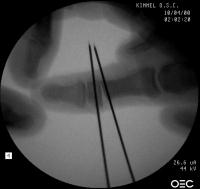

Intraoperative fluoroscopy. The mass:

Click for larger image

Osteotomy planning: proximal pin parallel to the proximal joint line, distal pin parallel to the distal joint line:

Pins were used as saw blade alignment guides:

Osteotomy closed: